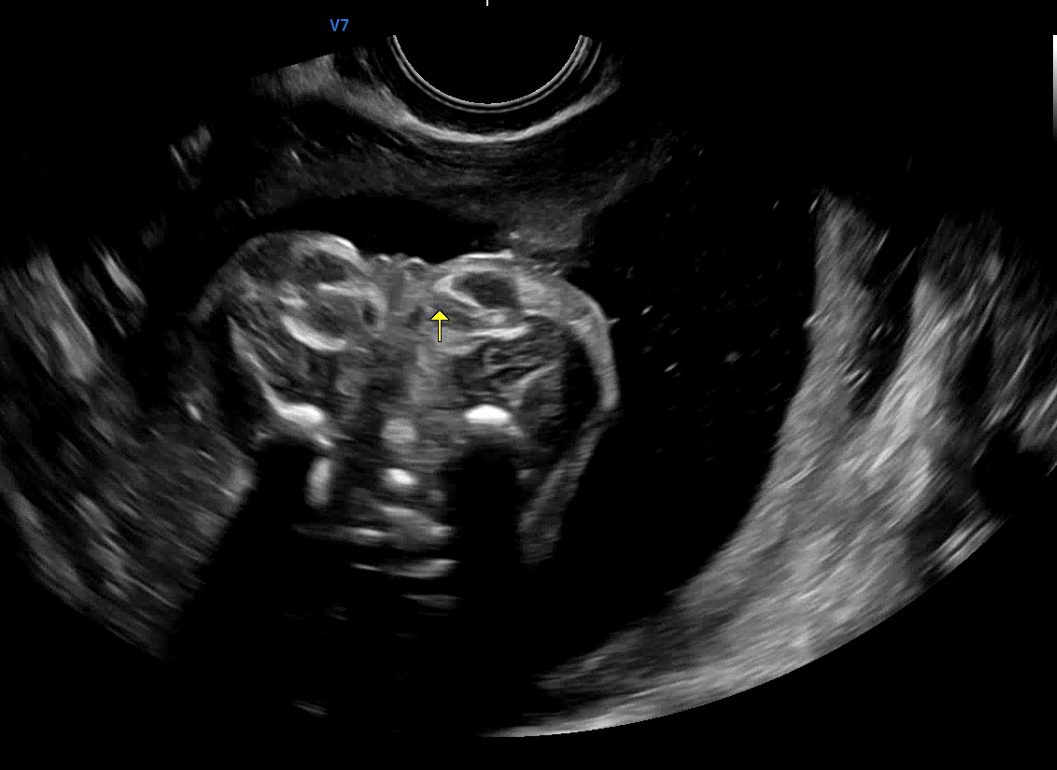

왕배의 성별이 너무 궁금했으나 우리 부부도 16주 때는 알 수가 없었다.

초음파 사진을 보면 뭐가 약간 튀어나와있는 거 같으면서도 아닌 거 같았고, 의사 선생님께 여쭤봐도 처음에는 남아인거 같았는데 자세히 보니깐 아닌거 같기도 하고 애매하다는 답변을 주셨다 🤷♂️🤷♂️

오랑이: 저 사진대로라면 남자아이면 안돼. 너무 작아...

우리 부부는 51:49 정도의 의견으로 첫째는 딸이기를 임신 초반부터 원했었다. 나는 남아라도 상관없었지만 초음파

사진의 크기라면 여아인 게 훨씬 낫다고 판단했다. 남아이기에는 아빠를 너무 안 닮았기도 하고.